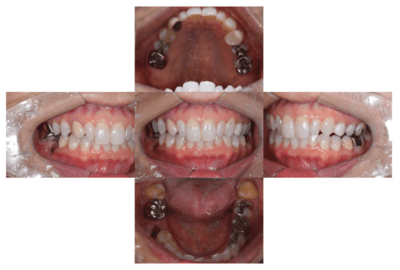

初診時の口腔内

説明:

初診時の口腔内です。かぶせ物があり、一見虫歯とはわからないです。

CT像①

CT像②

CT像です。根の中央を超えて虫歯が広がっているのがわかります。そこに上の親知らずを移植することに

しました。